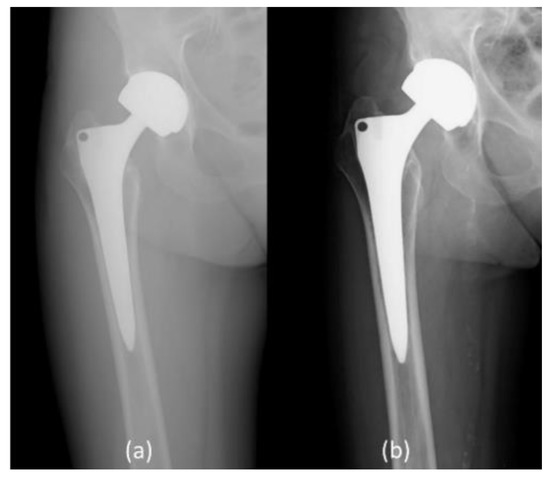

2.2. Radiological Outcomes